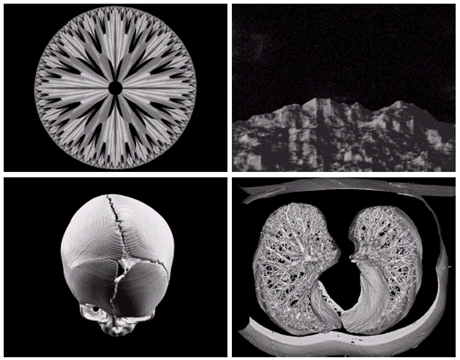

Gamma ray image

• 감마선의 투과성을 이용

• 주요 응용분야: 핵의학, 천문관측

Image

a) 환자에게 감마선을 방사하는 방사선 동위원소를 주사, 감마 검출기로써 영상을 획득 - 병소의 위치 파악에 유용 b) PET(positron emission tomography) image c) 백조자리 15,000년전의 가스성운의 감마선 영상 d) 핵반응 밸브로부터 나오는 감마선(밝은 부분)